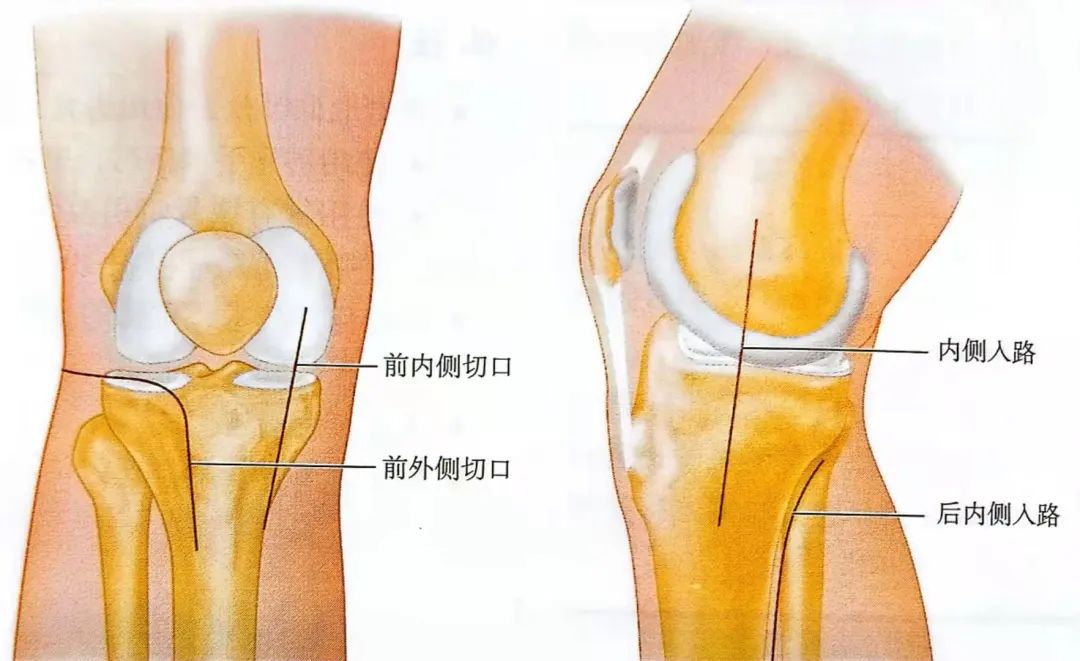

通常采用小切口复位关节面。切口要根据骨折情况来选择,通常包括:①前外侧或者前内侧切口;②内侧或后内侧切口。

▲示意图